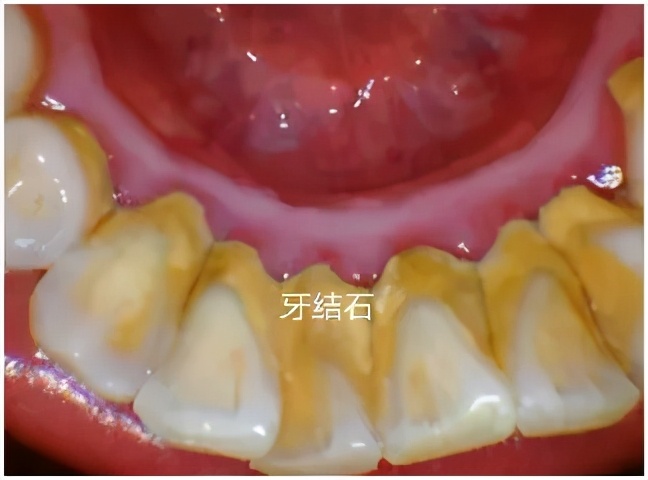

下图牙表面黄色的,就是 牙结石